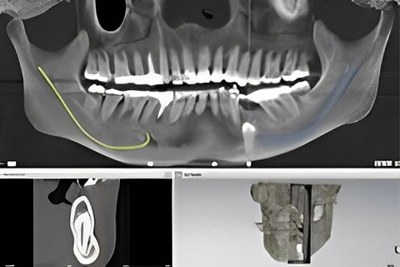

歯科用CTとは、歯や顎の構造を三次元で詳細に撮影するための医療用画像装置です。

正式には「歯科用コーンビームCT(Cone Beam Computed Tomography)」と呼ばれ、従来の2次元のレントゲン撮影では把握しにくい歯や顎の内部構造を立体的に捉えることができます。

歯科用CTは、顎の骨、歯の根、神経の位置などを3Dで詳細に確認できます。これにより、従来のレントゲンでは見つけにくい問題を発見しやすくなります。 - 精度の高い診断

インプラント治療、歯根治療、親知らずの抜歯、顎関節症の診断など、さまざまな歯科治療で精度の高い診断が可能になります。 - 低線量

歯科用CTは歯やあごの骨を三次元で詳しく見ることができるため、虫歯の進行具合、根管治療が必要な範囲、親知らずの位置、骨の密度などを正確に診断できます。

インプラントを行う際など、あごの骨の状態を詳細に確認することで、適切な位置や角度を計画できます。

歯科用CTを使うことで、神経や血管の位置を事前に把握できるため、治療中の合併症やリスクを最小限に抑えることができます。